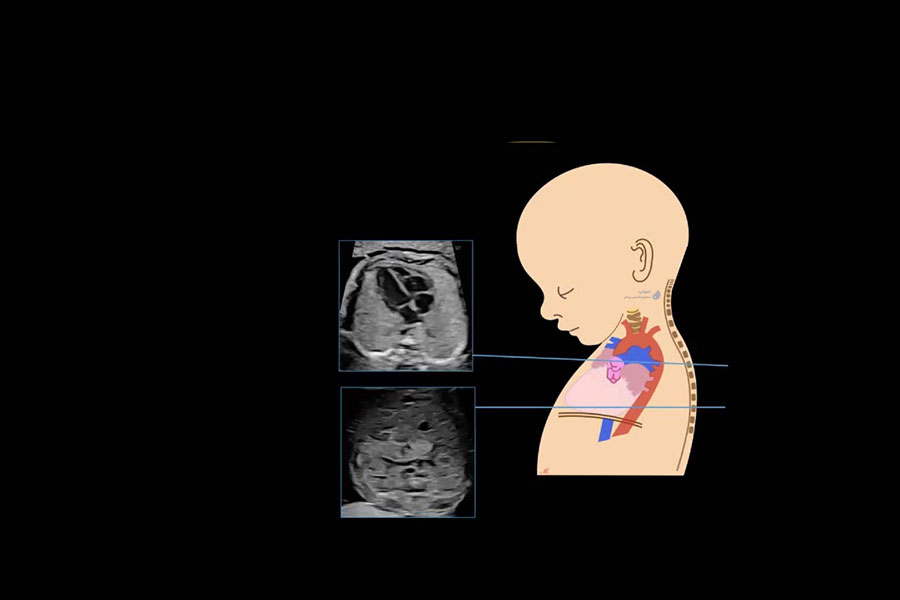

اکوکاردیوگرافی قلب جنین یکی از تخصصی ترین روش های تصویربرداری در دوران بارداری است که به پزشکان اجازه می‌دهد عملکرد و ساختار قلب جنین را در مراحل مختلف رشد بررسی کنند. این روش نقش کلیدی در تشخیص زودهنگام بیماری های مادرزادی قلبی ایفا می‌کند و به متخصصان این امکان را می‌دهد که در صورت لزوم، اقدامات درمانی یا تصمیمات مدیریتی مناسب را در مورد بارداری اتخاذ کنند.

اکوکاردیوگرافی جنینی یک روش تصویربرداری پیشرفته است که برای ارزیابی ساختار و عملکرد قلب جنین در رحم مادر استفاده می‌شود. این روش در هفته های خاصی از بارداری انجام می‌شود و به پزشکان کمک می‌کند تا بیماری های مادرزادی قلب را زودتر از موعد تشخیص دهند و در مورد ادامه بارداری، زایمان و درمان پس از تولد تصمیم گیری کنند.

آناتومی طبیعی قلب جنین در سونوگرافی: ساختار قلب جنین طی هفته‌های بارداری تکامل می‌یابد و بررسی صحیح آناتومی قلب نیاز به شناخت کامل بطن‌ها، دهلیزها، دریچه‌ها و عروق اصلی دارد. در این بخش، نحوه ارزیابی عملکرد قلب، شناسایی ارتباط بین حفرات قلبی و تشخیص جریان خون نرمال بررسی می‌شود. درک آناتومی طبیعی، پایه‌ای برای تشخیص بیماری‌های مادرزادی قلبی است.